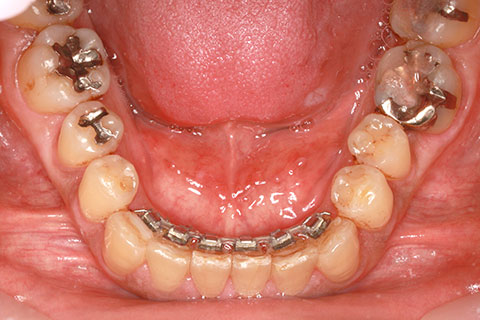

ハーフリンガル矯正3:上の歯のみ舌側矯正で治療(矯正期間24ヶ月)

治療前

治療中(開始直後)

治療中(開始半年後)

治療後

- 年齢・性別

- 25歳女性

- 治療期間

- 2年0ヶ月

- 抜歯

- 上下4番抜歯

- 治療費

- 110万円

- 治療内容

- 施術の副作用(リスク)

- 表側矯正と比較して、力学的な操作性が複雑なため、ボーイングエフェクトを起こしやすい。